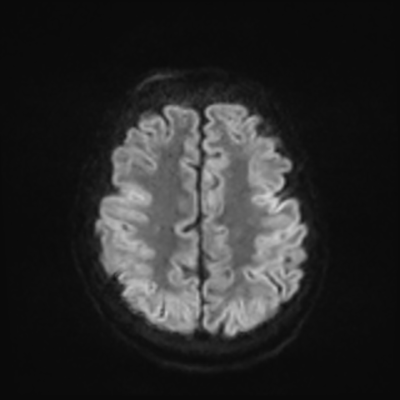

MRI brain (DWI)

You can clearly see diffuse cortical and basal ganglia diffusion restriction, and that of his deep cerebellar nuclei as well. The right occipital lobe abnormalities are a little more prominent, but then you remember that he is known to have had a right occipital stroke weeks ago.

In reviewing his data, you know that he doesn't have any of the strong predictors of a poor neurologic prognosis. However, based on these findings on MRI, along with the absent reactivity on cEEG, you are able to tell the primary team and the patient's family that he is likely to have a poor prognosis, based on these multiple moderate predictors. Recovery is not completely impossible-- there is more uncertainty with this prognostication than if we were able to get SSEPs-- but you're very worried about his outlook and that any potential recovery would require a very protracted rehabilitation period. Given his high cervical cord injury level, tracheostomy would be required anyway. So, it comes down to whether his family thinks he'd want to pursue these aggressive measures.